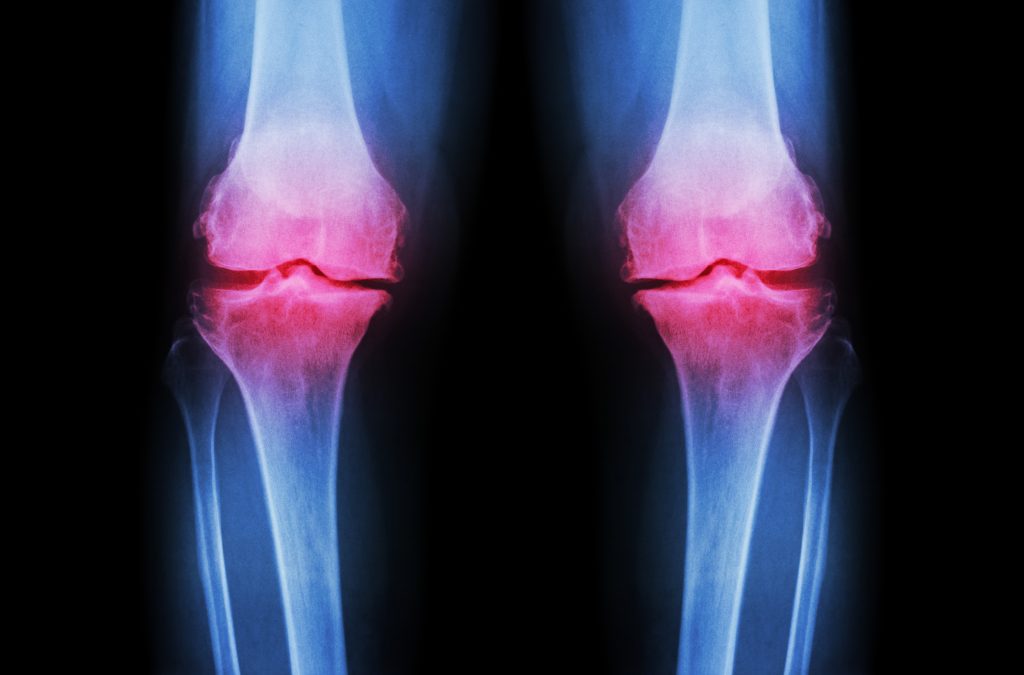

Euflexxa helps restore joint function and relieve arthritis pain, especially in the knees and hips. It’s often part of a wider treatment plan including physiotherapy.

Euflexxa is used to relieve pain due to osteoarthritis by supplementing the joint’s natural lubricant, hyaluronic acid. Euflexxa can be injected into the knee, hip, shoulder, ankle and 1st CMC joints.